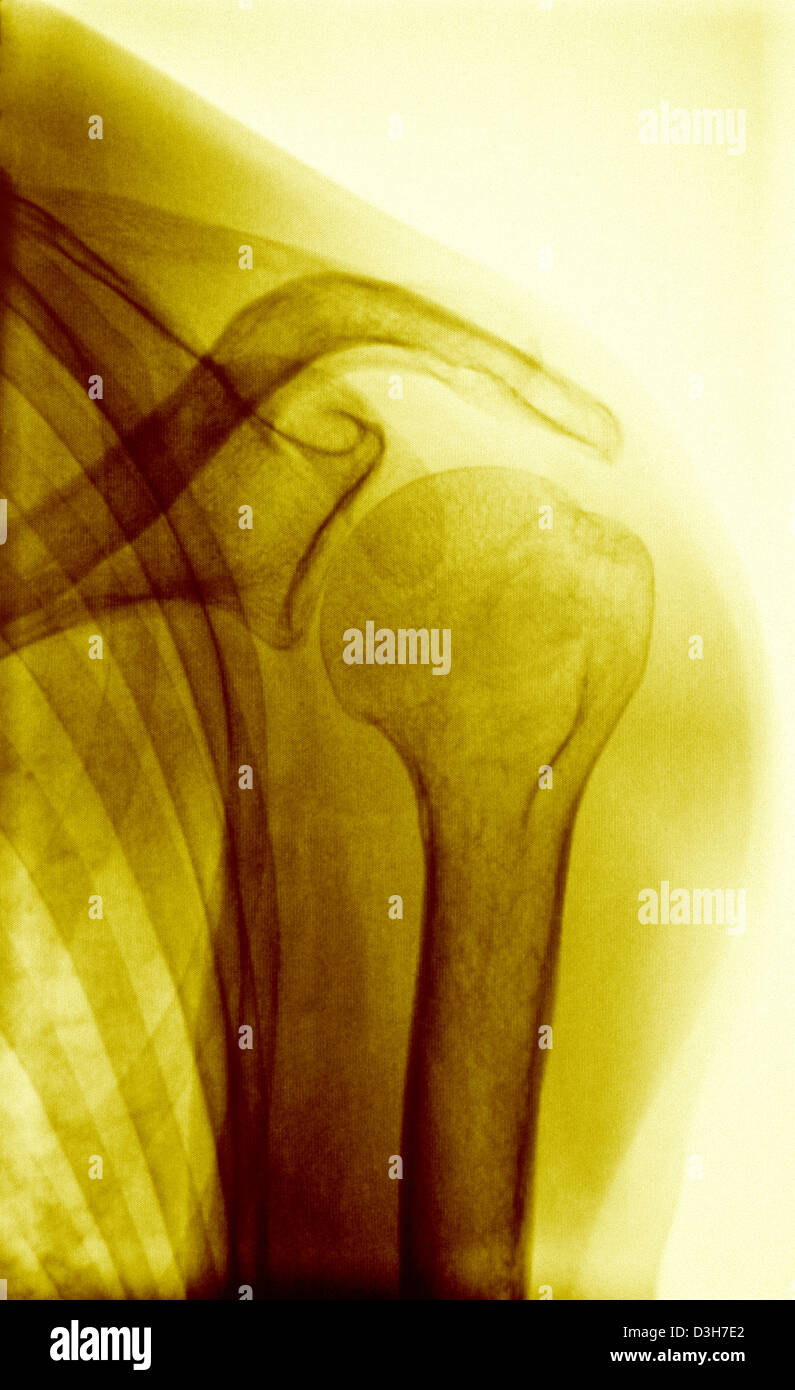

From www.sciencephoto.com

Shoulder, Xray Stock Image C054/8092 Science Photo Library Shoulder X Ray Special Views See the anatomical structures and radiographic features of shoulder disorders,. Learn how to perform and interpret the shoulder ap glenoid view, also known as a true ap or a 'grashey view', to assess the glenohumeral joint. Find out the key features of a. Although a majority of your focus may be on the shoulder girdle, be vigilant in inspecting the. Shoulder X Ray Special Views.